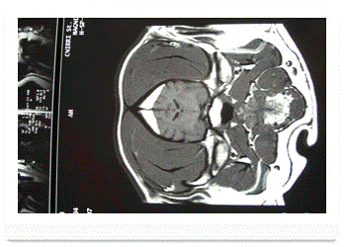

В отличие от ЭЭГ-исследований нейрорадиологические методы не могут ни подтвердить, ни опровергнуть диагноз эпилепсия. Они не информативны для диагностики эпилепсии, а предназначены для установления этиологии заболевания и для ведения предоперационного периода. Кроме того, любая форма эпилепсии требует обязательного проведения магнитно-резонансной томографии (МРТ).

На фото магнитно-резонансная томография мозга собаки с идеопатической эпилепсией, изменений нет.